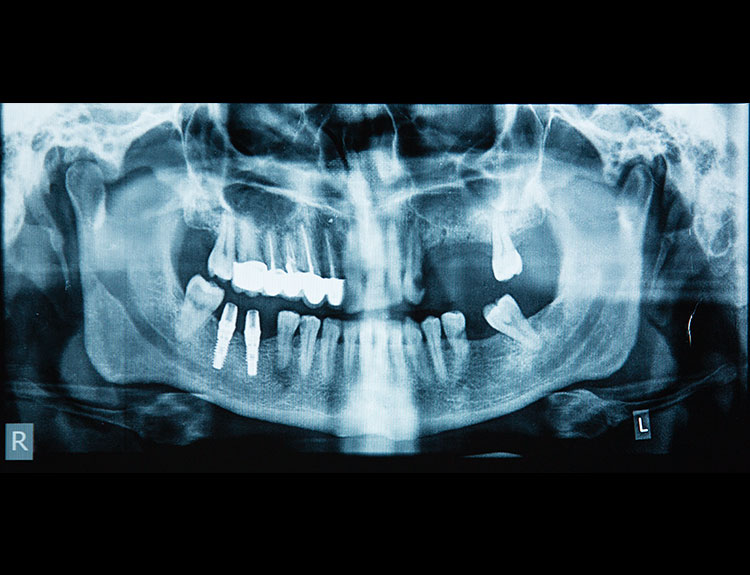

Dental implants are artificial tooth roots made of medical-grade titanium that are surgically placed into the jawbone. Once the implant integrates with the bone, a crown is fixed on top, giving you a strong, natural-looking replacement tooth.

If you are searching for reliable Dental Implants in Punjabi Bagh, Dental Que provides personalized solutions based on your oral health, bone condition, and smile goals.